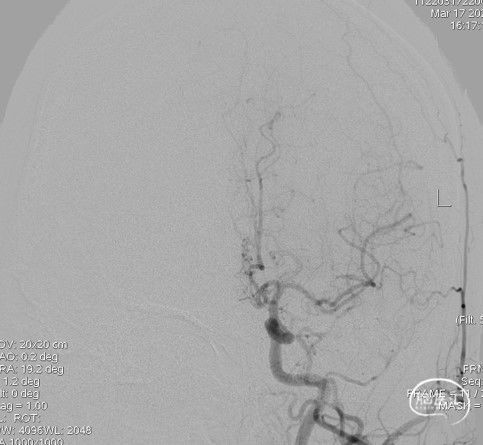

造影:右侧颈内动脉末端变细,大脑前及大脑中自起始部闭塞,脑底少量烟雾血管形成,汇聚使R-MCA少量分支显影。

右侧颈内动脉侧位: